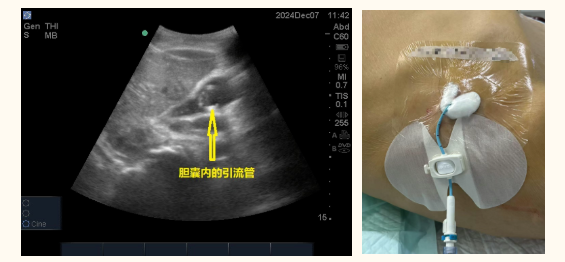

超声引导下经皮穿刺胆囊置管引流,是一种在实时超声监视下进行的微创介入技术。医生通过超声图像精准定位,避开重要血管,将一根细穿刺针经皮肤、肝脏直达胆囊内,随后,沿穿刺针置入一根柔软的多侧孔引流管,另一端连接引流袋。通过这根管道,淤积在胆囊内的感染胆汁得以持续排出,胆囊内压力迅速降低,炎症得到控制。这一过程可理解为“为发炎的胆囊安装临时下水道”。不同于传统手术切除病灶,该技术旨在通过解除胆囊内高压状态,打破“梗阻-感染-水肿”的恶性循环,为后续治疗创造条件。整个操作仅需局部麻醉,患者保持清醒状态,可以随时与医生交流感受。穿刺点仅约3毫米,无需缝合,愈合后几乎不留疤痕。